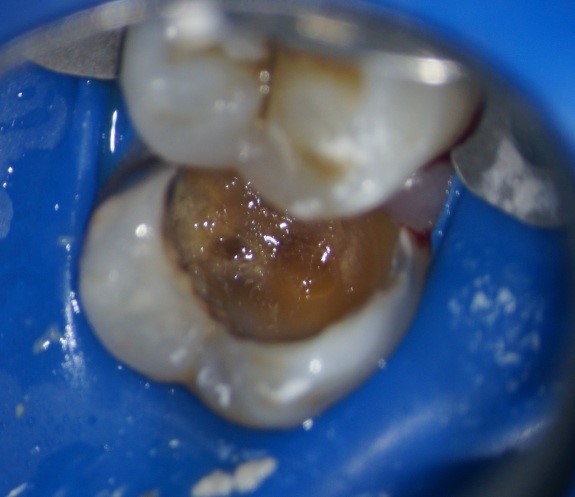

Также зачастую кариозный процесс на контактной поверхности затрагивает оба зуба(на фото справа), как и в данном случае, но за счет ранней диагностики удалось вовремя предотвратить развитие осложнений и ограничиться лишь постановкой пломб.